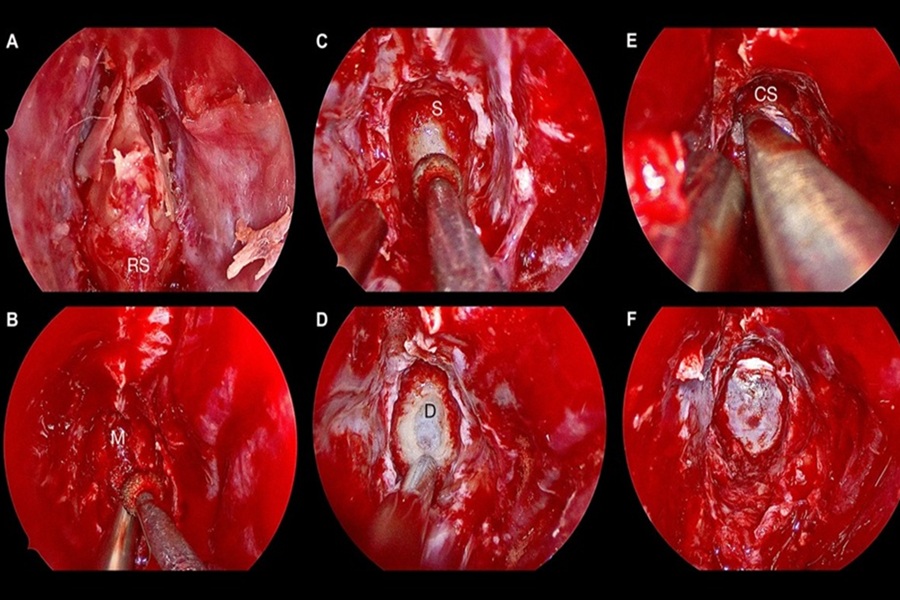

در این شرایط، جراحی هدف اصلی خود را بر برداشتن فشار از روی عصبهای بینایی قرار میدهد. دکتر القاسی از جراحی آندوسکوپیک مغز، از طریق بینی و سینوس اسفنوئید، برای دسترسی به این تومورها استفاده میکنند. این روش کم تهاجمی است و امکان دید بهتر و بهبودی سریعتر را فراهم میآورد. جراحی تومور هیپوفیز، ترکیبی از تخصص جراحی مغز و اعصاب و غدد درونریز را میطلبد تا هم بینایی حفظ شود و هم عملکرد هورمونی بدن به حالت عادی بازگردد.

دکتر القاسی با تخصص در جراحیهای تومورهای سی پی انگل، بر روی خارج کردن تومور با حداکثر حفظ عصبهای حیاتی تمرکز میکنند. در این جراحیها، از تکنیکهای پیشرفته مانیتورینگ عصبی استفاده میشود تا خطر آسیب به عصبهای صورت، شنوایی و تعادل به کمترین میزان برسد. حتی تومورهای خوشخیم در این ناحیه نیز به دلیل اثر فشاری، باید با دقت مورد توجه قرار گیرند و در صورت لزوم، مداخله جراحی برنامهریزی شود تا از نقصهای عصبی جدی و دائمی جلوگیری شود.

عمل جراحی تومور در سیستم عصبی مرکزی (مغز و نخاع) یکی از ظریفترین و پیچیدهترین جراحیهای پزشکی است. دلیل اصلی این حساسیت، ماهیت حیاتی بافتهای اطراف تومور است. مغز و نخاع مرکز کنترل تمامی عملکردهای بدن، از جمله حرکت، گفتار، حافظه و تنفس هستند. حتی کوچکترین آسیب به یک ناحیه حساس میتواند منجر به نقصهای عصبی شدید و دائمی شود. بنابراین، هدف اصلی جراح همیشه برقراری یک تعادل دشوار بین برداشتن حداکثری تومور و حفظ عملکرد عصبی است.

برای دستیابی به این تعادل، جراح باید از تکنیکها و ابزارهای پیشرفتهای استفاده کند. این ابزارها شامل میکروسکوپهای جراحی با قدرت بزرگنمایی بالا، سیستمهای ناوبری عصبی (نوروناویشن) که مانند GPS جراحی عمل میکنند و مانیتورینگ عصبی حین عمل هستند. این فناوریها به جراح کمک میکنند تا با دقتی میلیمتری، مرزهای بین تومور و بافت سالم را تشخیص دهد. انتخاب یک جراح با سابقه درخشان در جراحیهای پیشرفته مغز و اعصاب، مانند دکتر القاسی، در مواجهه با این حساسیتهای عمل، یک تصمیم حیاتی برای آینده بیمار است.